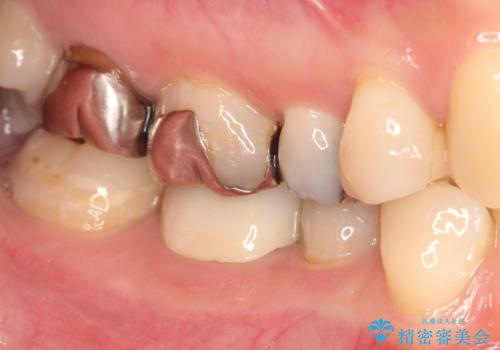

- 下顎の銀歯と、かぶせ物が外れたままになっている歯の治療を主訴に来院されました。

左下の奥歯はかぶせ物が外れて、土台が露出している状態でした。